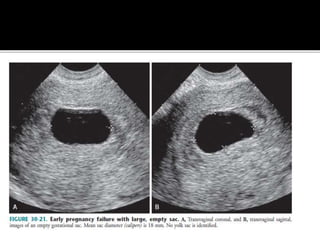

2.Gestational sac features

 Abnormal size :

Nyberg et al refined the definition of an

abnormal gestational sac as MSD of 25.0mm

or more without an embryo, or MSD of 20.0

mm or more without a yolk sac.

 An anembryonic

pregnancy may be

diagnosed when there

is no fetal

pole identified on trans-

vaginal scanning the size

of the gestational sac is

such that a fetal pole

should be seen.

 MSD ≥ 25 mm (by RCOG

criteria)

 There is little or no growth

of the gestational sac

between interval scans

 Normally the MSD should

increase by 1 mm per day

 If MSD is too small to

ascertain viability on the

initial ultrasound, a follow

up scan in 10-14 days

should differentiate early

pregnancy from a failed

pregnancy